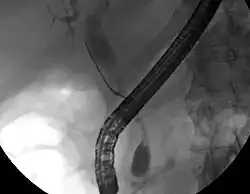

Embora a imagem abdominal possa ser útil no diagnóstico de colangiocarcinoma, a imagem direta dos ductos biliares é frequentemente necessária. A colangiopancreatografia retrógrada endoscópica (CPRE), um procedimento endoscópico realizado por um gastroenterologista ou cirurgião especialmente treinado, tem sido amplamente utilizada para esse fim. Embora a CPRE seja um procedimento invasivo com riscos concomitantes, suas vantagens incluem a capacidade de obter biópsias e colocar stents ou realizar outras intervenções para aliviar a obstrução biliar.[12] A ultrassonografia endoscópica também pode ser realizada no momento da CPRE e pode aumentar a precisão da biópsia e produzir informações sobre a invasão e a operabilidade do linfonodo.[54] Como alternativa à CPRE, a colangiografia percutânea trans-hepática (CPT) pode ser utilizada. A colangiopancreatografia por ressonância magnética (CPRM) é uma alternativa não invasiva à CPRE.[55][56][57] Alguns autores sugeriram que a CPRM deve suplantar a CPRE no diagnóstico de cânceres biliares, pois pode definir com mais precisão o tumor e evitar os riscos da CPRE.[58][59][60]